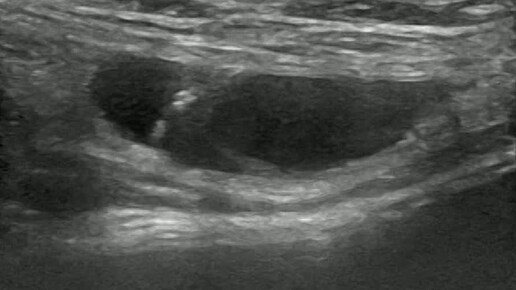

Видео к статье: Гидроцеле канала Нукка. https://dzen.ru/a/aDAxMOvxqQcgJkGG

Ультразвуковые находки от врача УЗД Зорина Я.П.